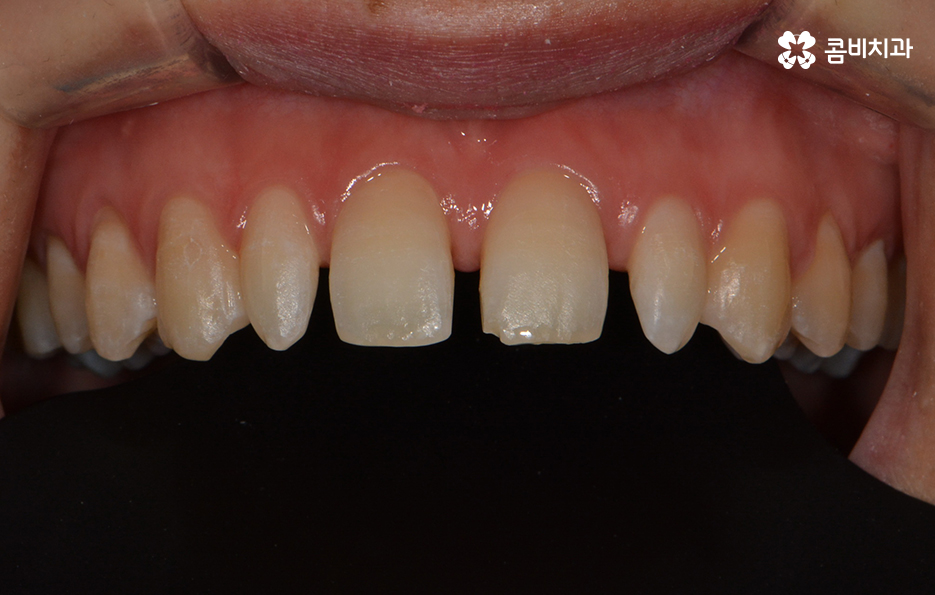

앞니의 깨짐과 왜소치, 전체적인 치열의 개선을 원하셨던 케이스

위 케이스는 왜소치로 인해 치아 사이가 벌어져 보이는 것과

전체적인 치열의 심미적 개선을 함께 원하셨던 경우입니다.

파란 원 - 치아의 깨짐, 빨간 원 - 왜소치

왜소치란? - 일반적인 치아에 비해 비정상적으로 작은 치아를 의미 합니다. 왜소치가 앞니 부분에 위치한 경우 치아가 벌어져 보이거나 심미적인 부담감을 느끼실 수 있습니다.